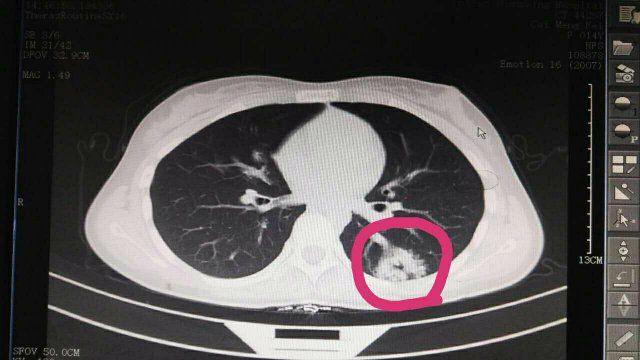

蔡**,女,14歲因“反覆頭暈3年余”,求診莆田及莆田各三級(jí)醫(yī)院,做過很多輔助檢查,均未確診,于2017-2-26日就診我院門診,接診是我院兒科林富醫(yī)師,經(jīng)過認(rèn)真仔細(xì)查體,發(fā)現(xiàn)患兒左側(cè)肩胛骨可聞及Ⅱ-Ⅲ/Ⅵ級(jí)收縮期雜音,為明確診斷,即刻請我院莊姞副主任醫(yī)師(原莆田市Di一醫(yī)院NICU主任)會(huì)診,查胸部CT發(fā)現(xiàn)左肺下葉背段血管畸形。莊姞副主任醫(yī)師告訴我們,部分型肺血管畸形如果不認(rèn)真查體是很難查體的到,年輕醫(yī)師能如此仔細(xì)查體,確診多家醫(yī)院未確診的疾病,不得不對(duì)林醫(yī)生豎起大拇指,通過此次經(jīng)歷,可見臨床醫(yī)生必須熟練掌握臨床三基的重要性。